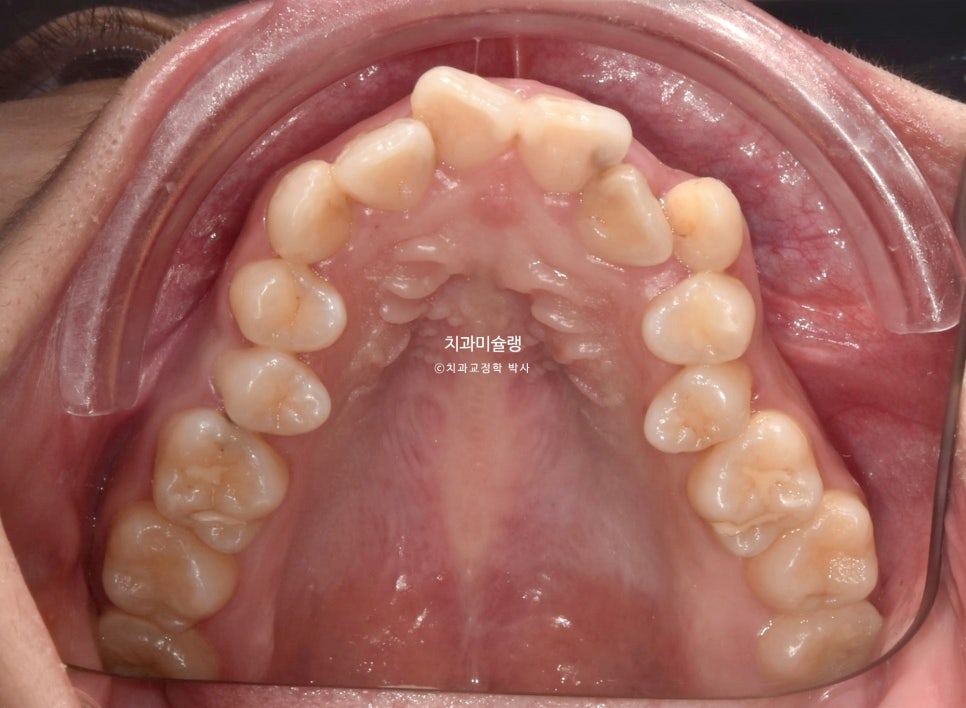

악궁이 소구치 부위가 안으로 쓰러져 찌그러진 모양입니다.

악궁형태나 배열이 이상적입니다.